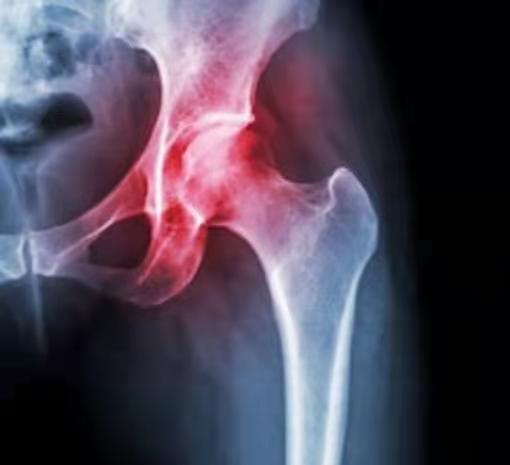

2.2.1X线平片

X线平片是最常用的检查方式,有利于及时发现问题及排除其他的疾患。但在平片中发现不了由髂腰肌或髂胫束引发弹响的特征性表现。